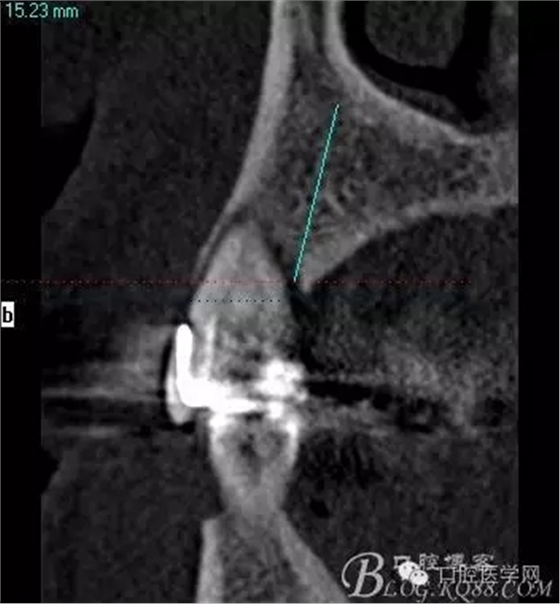

術(shù)后片顯示方向非??梢?p style="text-align:center">

頰顎向的方向也很理想 箭頭所示 空間填滿了自體骨